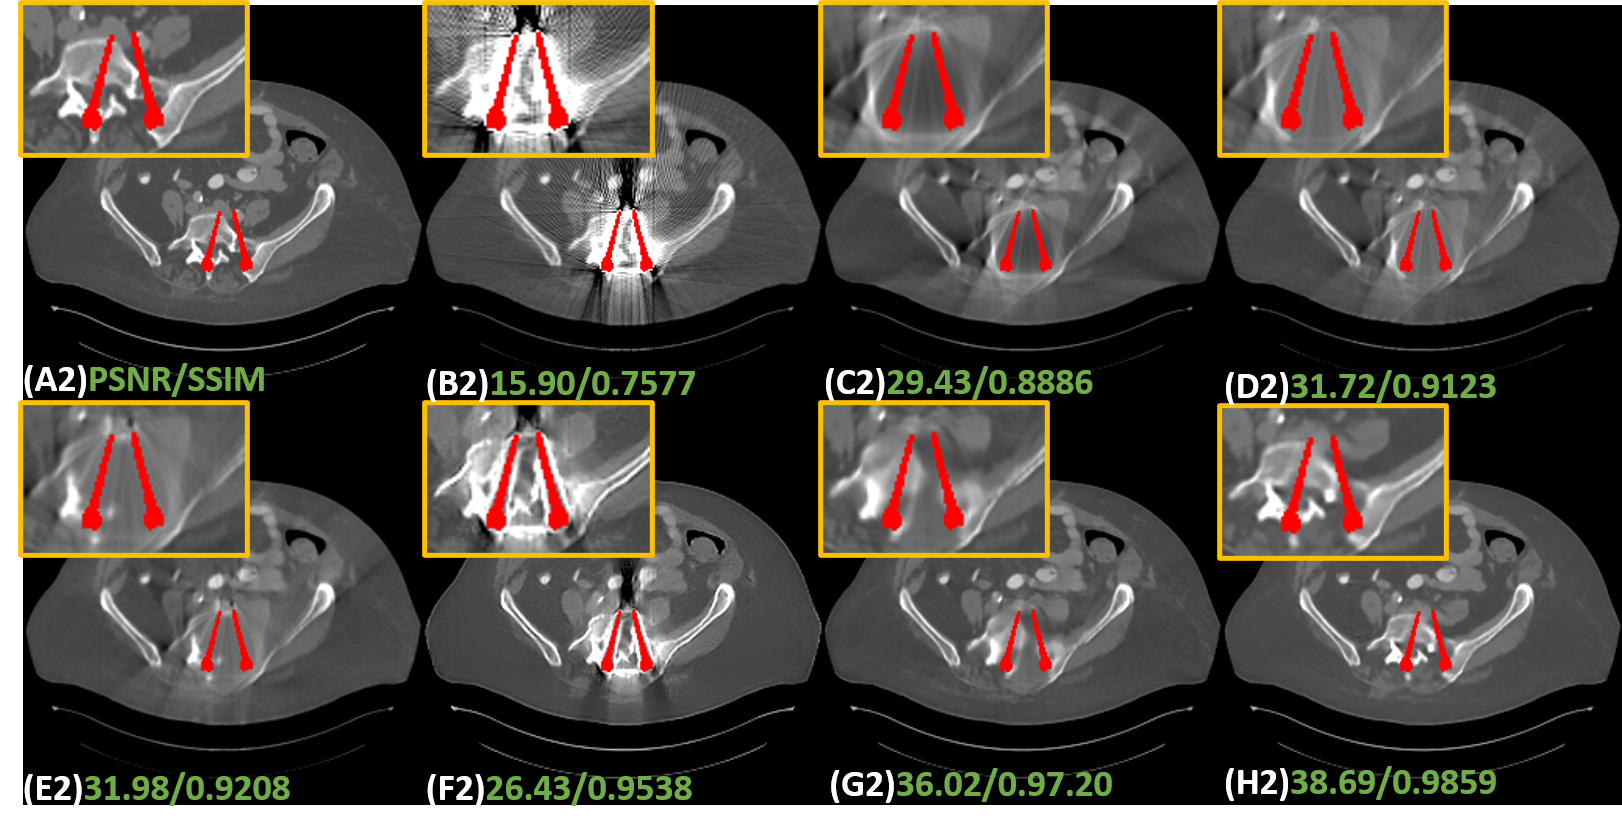

To validate the effectiveness of the proposed IDOL-Net, several methods, including LI [9], NMAR [16], CNNMAR [37], ADN [12], DuDoNet [13] were involved for comparison. LI and NMAR are widely used interpolation-based methods. CNNMAR takes advantage of the outputs of different MAR methods to generate a prior image. ADN is an advanced unsupervised image-domain method. DuDoNet is a state-of-the-art dual-domain approach. All the methods were implemented with the publicly released code or strictly implemented according to the original paper. Structural similarity (SSIM) and peak signal to noise ratio (PSNR) were employed as the quantitative metrics.

1) Quantitative comparisons: Table 1 shows the average quantitative results on the simulated dataset. It is observed that all the methods can significantly improve the PSNR and SSIM values and DL-based methods achieve better scores than traditional MAR methods. DuDoNet and IDOL-Net gain obvious improvements in terms of both metrics, which quantitatively demonstrated the merits of dual-domain methods. In addition, our method produces a noticeable advantage over DuDoNet in terms of both metrics for all the metal sizes, with an average improvement of 3.3dB in PSNR and 0.81 in SSIM.

2) Qualitative comparisons: Fig. 6 shows the representative results of different methods on simulated data with different metal sizes. For better visualization, the metal masks are painted in red. Due to the fact that LI and NMAR are interpolation-based methods directly discarding the projection data in metal trace, the metal information is lost and the corrected sinogram cannot keep the continuity at the boundaries of metal trace, leading to blurred tissues around the metals and remarkable secondary artifacts. Although CNNMAR fuses the results of different MAR methods, the improvement is quite limited. ADN achieves better performance on structure recovery around the metal implants than LI, NMAR and CNNMAR, and even DuDoNet in some cases, but it also can be noticed that in the second case (Fig. 6 (F2)), the shadow artifacts are not well suppressed and the details covered by the artifacts are hard to identify. This phenomenon probably lies in that ADN is essentially a post-processing method, which does not leverage the sinogram information. Compared to other methods, DuDoNet and the proposed IDOL-Net have the best performance on artifact reduction, but DuDoNet cannot recover the structures and tissues around the metal well, which can be clearly observed in the magnified yellow boxes in Fig. 6 (G2) and (G3). Our proposed IDOL-Net not only effectively removes most artifacts but also recovers the details better than all the other methods in all cases.